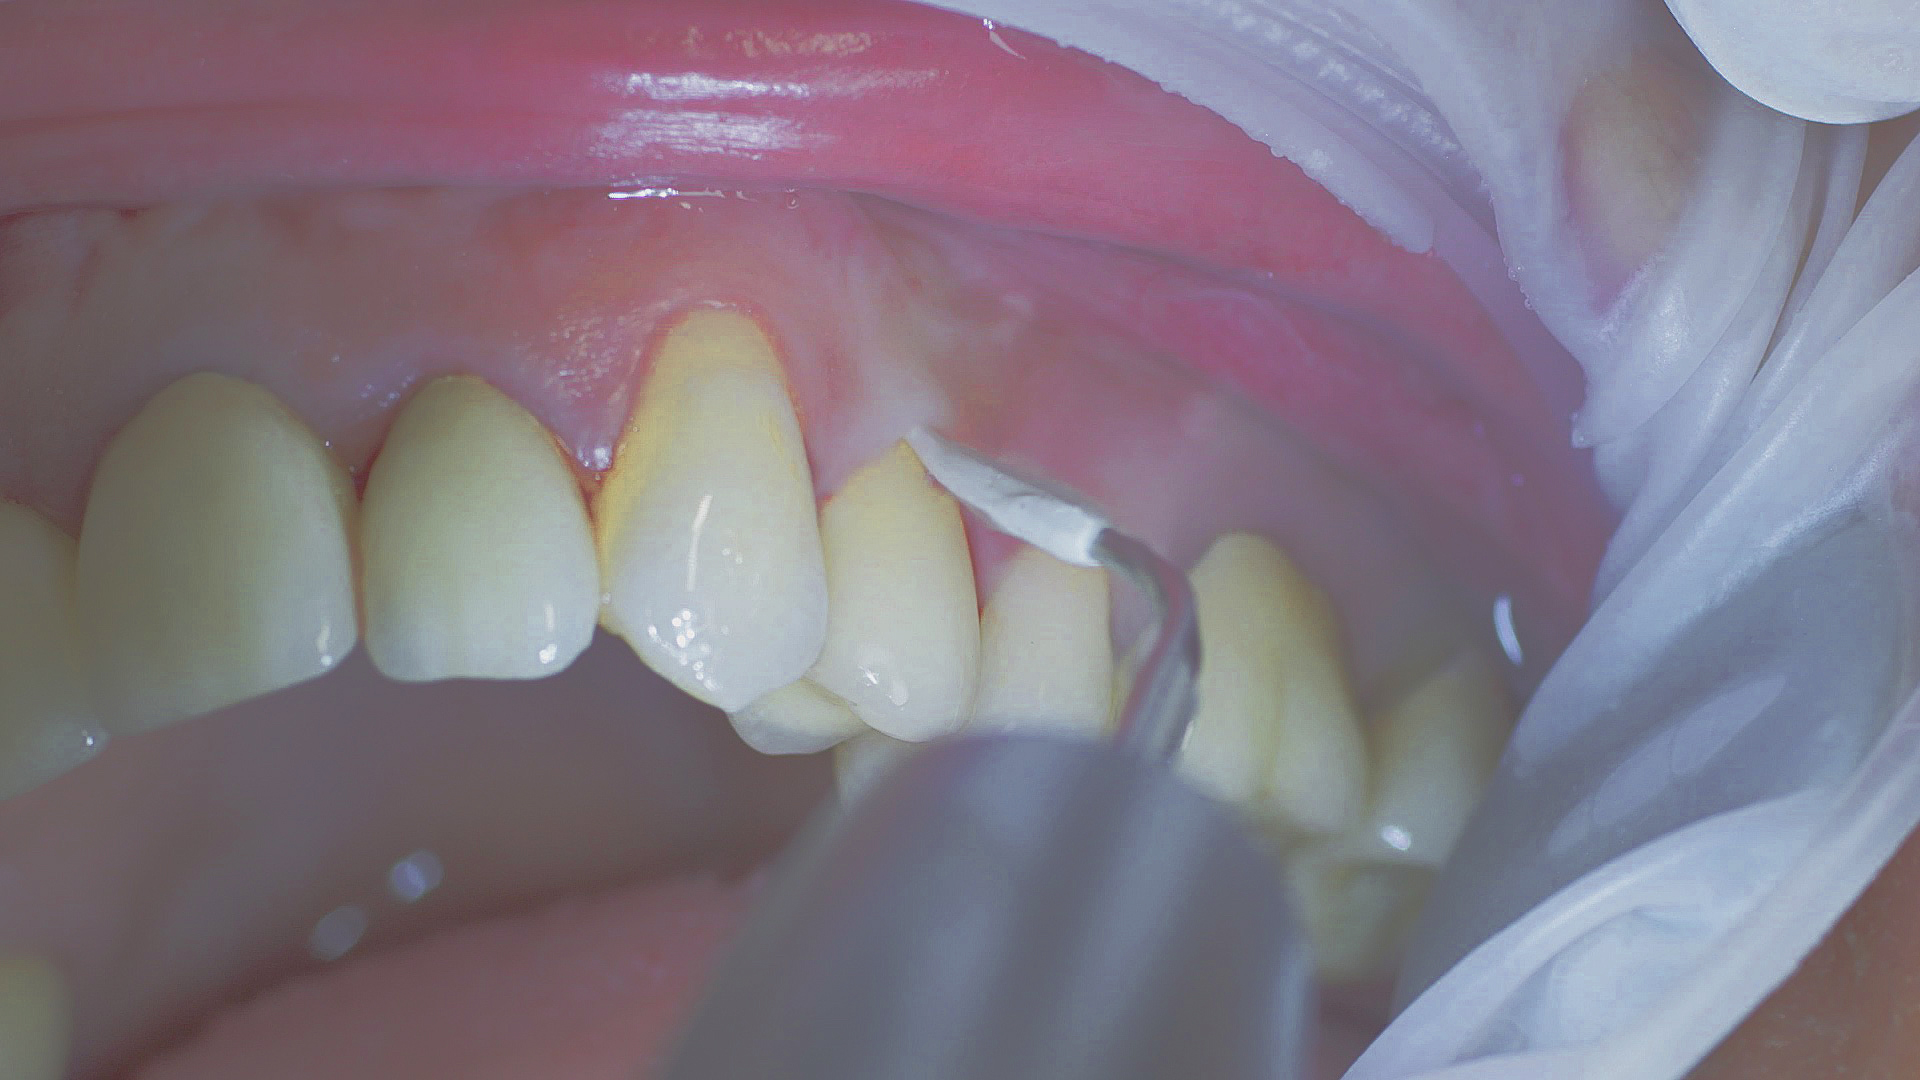

Every dental examination is based on a detailed medical history combined with targeted diagnostics con- taining as much detail as possible: The dentist records systemic risk factors such as diabetes or smoking and identifies any potential increased tendency to inflammation.[3] Hard and soft tissues are examined and periodontal pockets are probed in a screening test according to PSR (Periodontal Screening and Recording). In case of abnormal findings, the periodontal status is then re- corded and therapy is initiated where necessary. This treatment begins with professional biofilm management, by using, for example, rotary cups and polishing com pounds (Fig. 1), and comprehensive instructions in oral hygiene. Sonic or ultrasonic systems remain an effective alternative or supplement to manual instruments for sub- gingival debridement and biofilm management (presentation by Prof. Dr Ulrich Schlagenhauf; Fig. 2). Supplementary use of photodynamic therapy, air polishing or local and systemic antibiotics is not adequately documented (Prof. Dr Sema Hakki).[4] According to Dr Sergio Bizzarro, improved biomarker diagnostics may lead to an increase in customised patient therapy in the future.

Healthy peri-implant tissue does not show any signs of redness, swelling or bleeding, neither does it secrete pus when probed.[5] Based on the consensus document, Prof. Giovanni Salvi explained the importance of regu- lar probing — preferably with a flexible probe, as implant components often tend to obstruct the procedure.[5] In the case of mucositis or initial peri-implantitis already being present, the non-surgical removal of hard deposits and biofilm should be attempted first. For this purpose, ultra- sonic power and special instruments designed to protect the implant should be employed (Fig. 3; piezo scaler Tigon+ with 1I, W&H). In case of no remission, the recall frequency needs to be increased. However, specific recommendations, applicable to individual cases, are not yet available in this context.[15]